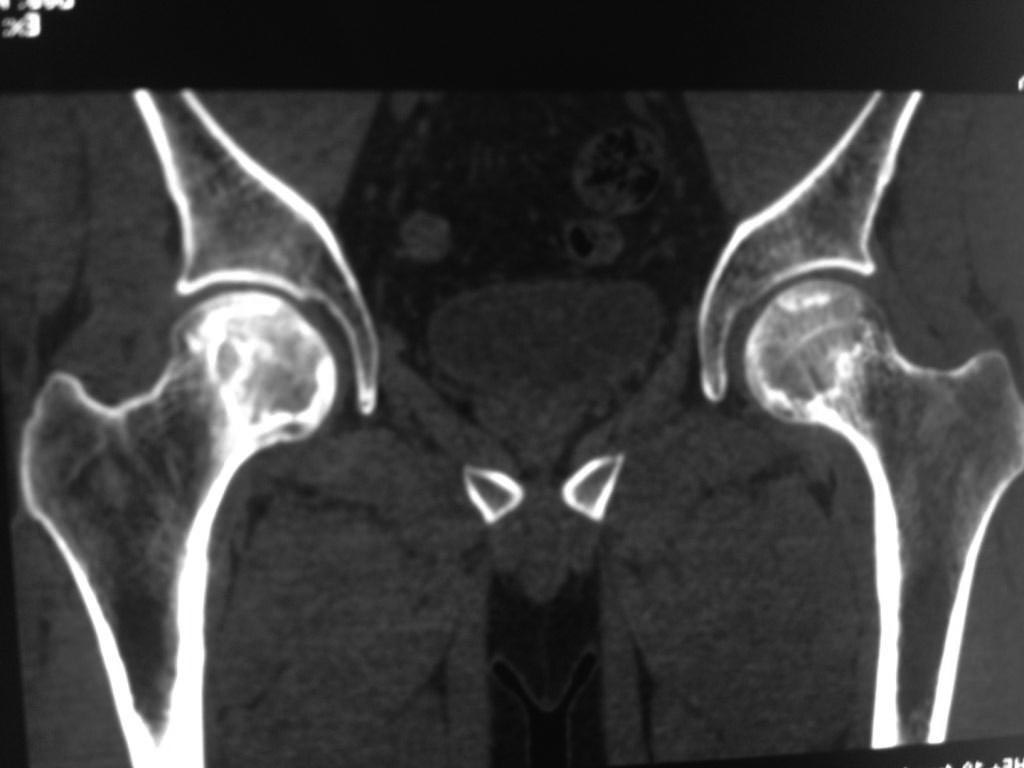

Возможно сомнения в диагностике связаны с нетипичной рентгенологической картиной. На снимке большая киста, которая расположена в центре головки, а при АВН начинается в верхней нагрузочной зоне. Отсутствует коллапс, сохранилась сферичность головки; не очень выраженный, но характерный признак "Crescent Sign".

Диффернциальную диагностику надо делать с доброкачественной кистой или метастазами. Но двухсторенная киста встречается очень редко, и киста в шейке распологается более дистально, чем при АВН. Гетерогенная картина головки немного напоминает метастаз, но без первичной опухоли и затяжной характер течения заболевания снимает подозрение на злокачественный процесс.

При наличии коллапса диагноз устанавить очень легко. Сканирование с изотопами тоже хороший метод исследования, который покажет "холодные" участки, окруженные "теплыми" зонами. Исследование в 25% дает погрешность, и поэтому на сегодня МРТ является "золотым стандартом" исследования. Пункция не помешает, но мне кажется, что здесь по классификации Ficat преколлапсный, т.е. вторая степень АВН.